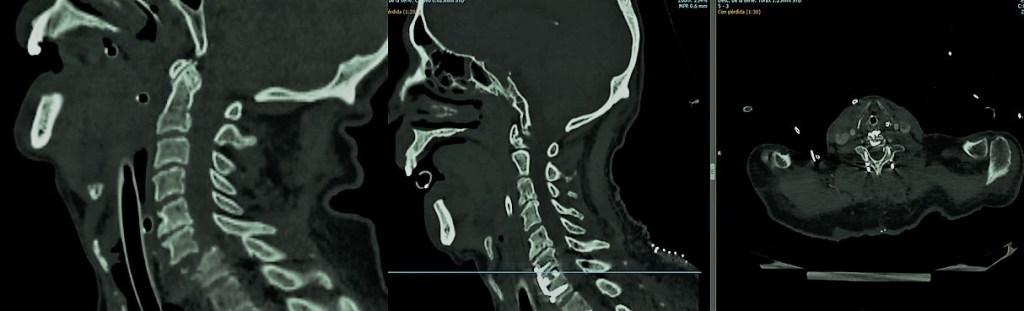

En el centro y a la derecha se aprecia el TAC postoperatorio en el se ha llevado a cabo la reducción de la luxación con un adecuado alineamiento y fijación combinada anterior mediante caja intersomática y placa así como posterior con tornillos a masas laterales.

-Inestabilidad craneocervical: Viene definida por la presencia de una movilidad excesiva en la charnela craneocervical, esto es, la articulación entre el hueso occipital (C0) y el complejo atlo-axoideo (C1-C2 y sus correspondientes ligamentos). Esto puede originar una deformidad, que a veces precisa de estudios dinámicos para ser puesta de manifiesto, con o sin dolor y/o déficit neurológico. Entre sus causas se encuentran afectaciones congénitas (como el «os odontoidum«, la enfermedad de Morquio, el síndrome de Down, Arnold Chiari, etc), afectaciones infilamatorias (artritis reumatoide o espondilitis anquilosante), traumáticas (fracturas), infecciosas (Síndrome de Grisel, típico en edad pediátrica) o tumorales (metástasis o tumores óseos primarios). Su tratamiento es generalmente quirúrgico a veces precedido de la reducción mecánica para corregir la deformidad.